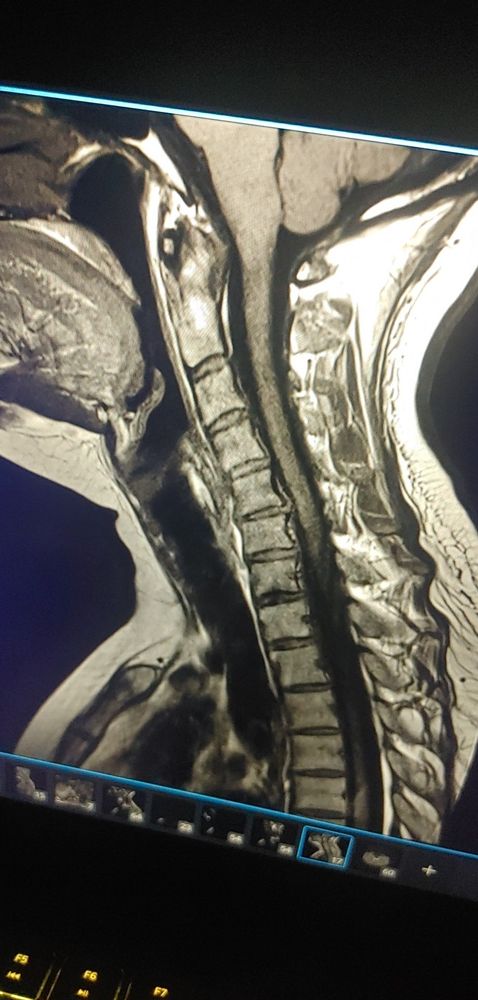

Some feet for my fetishists and a bit of an update. Met with a surgeon today, and I'll be going through several spine surgeries over the next year or two. I'll be around off and on, as my health allows. Kisses Findom. ๐

An MRI image of a c spine shows bulging discs, disc degeneration, bone spurs, a loss of natural curve, and impingement of the spinal cord.

Being real for a moment Findom. Make sure you are taking care of your body, so it can take care of you. Kisses!